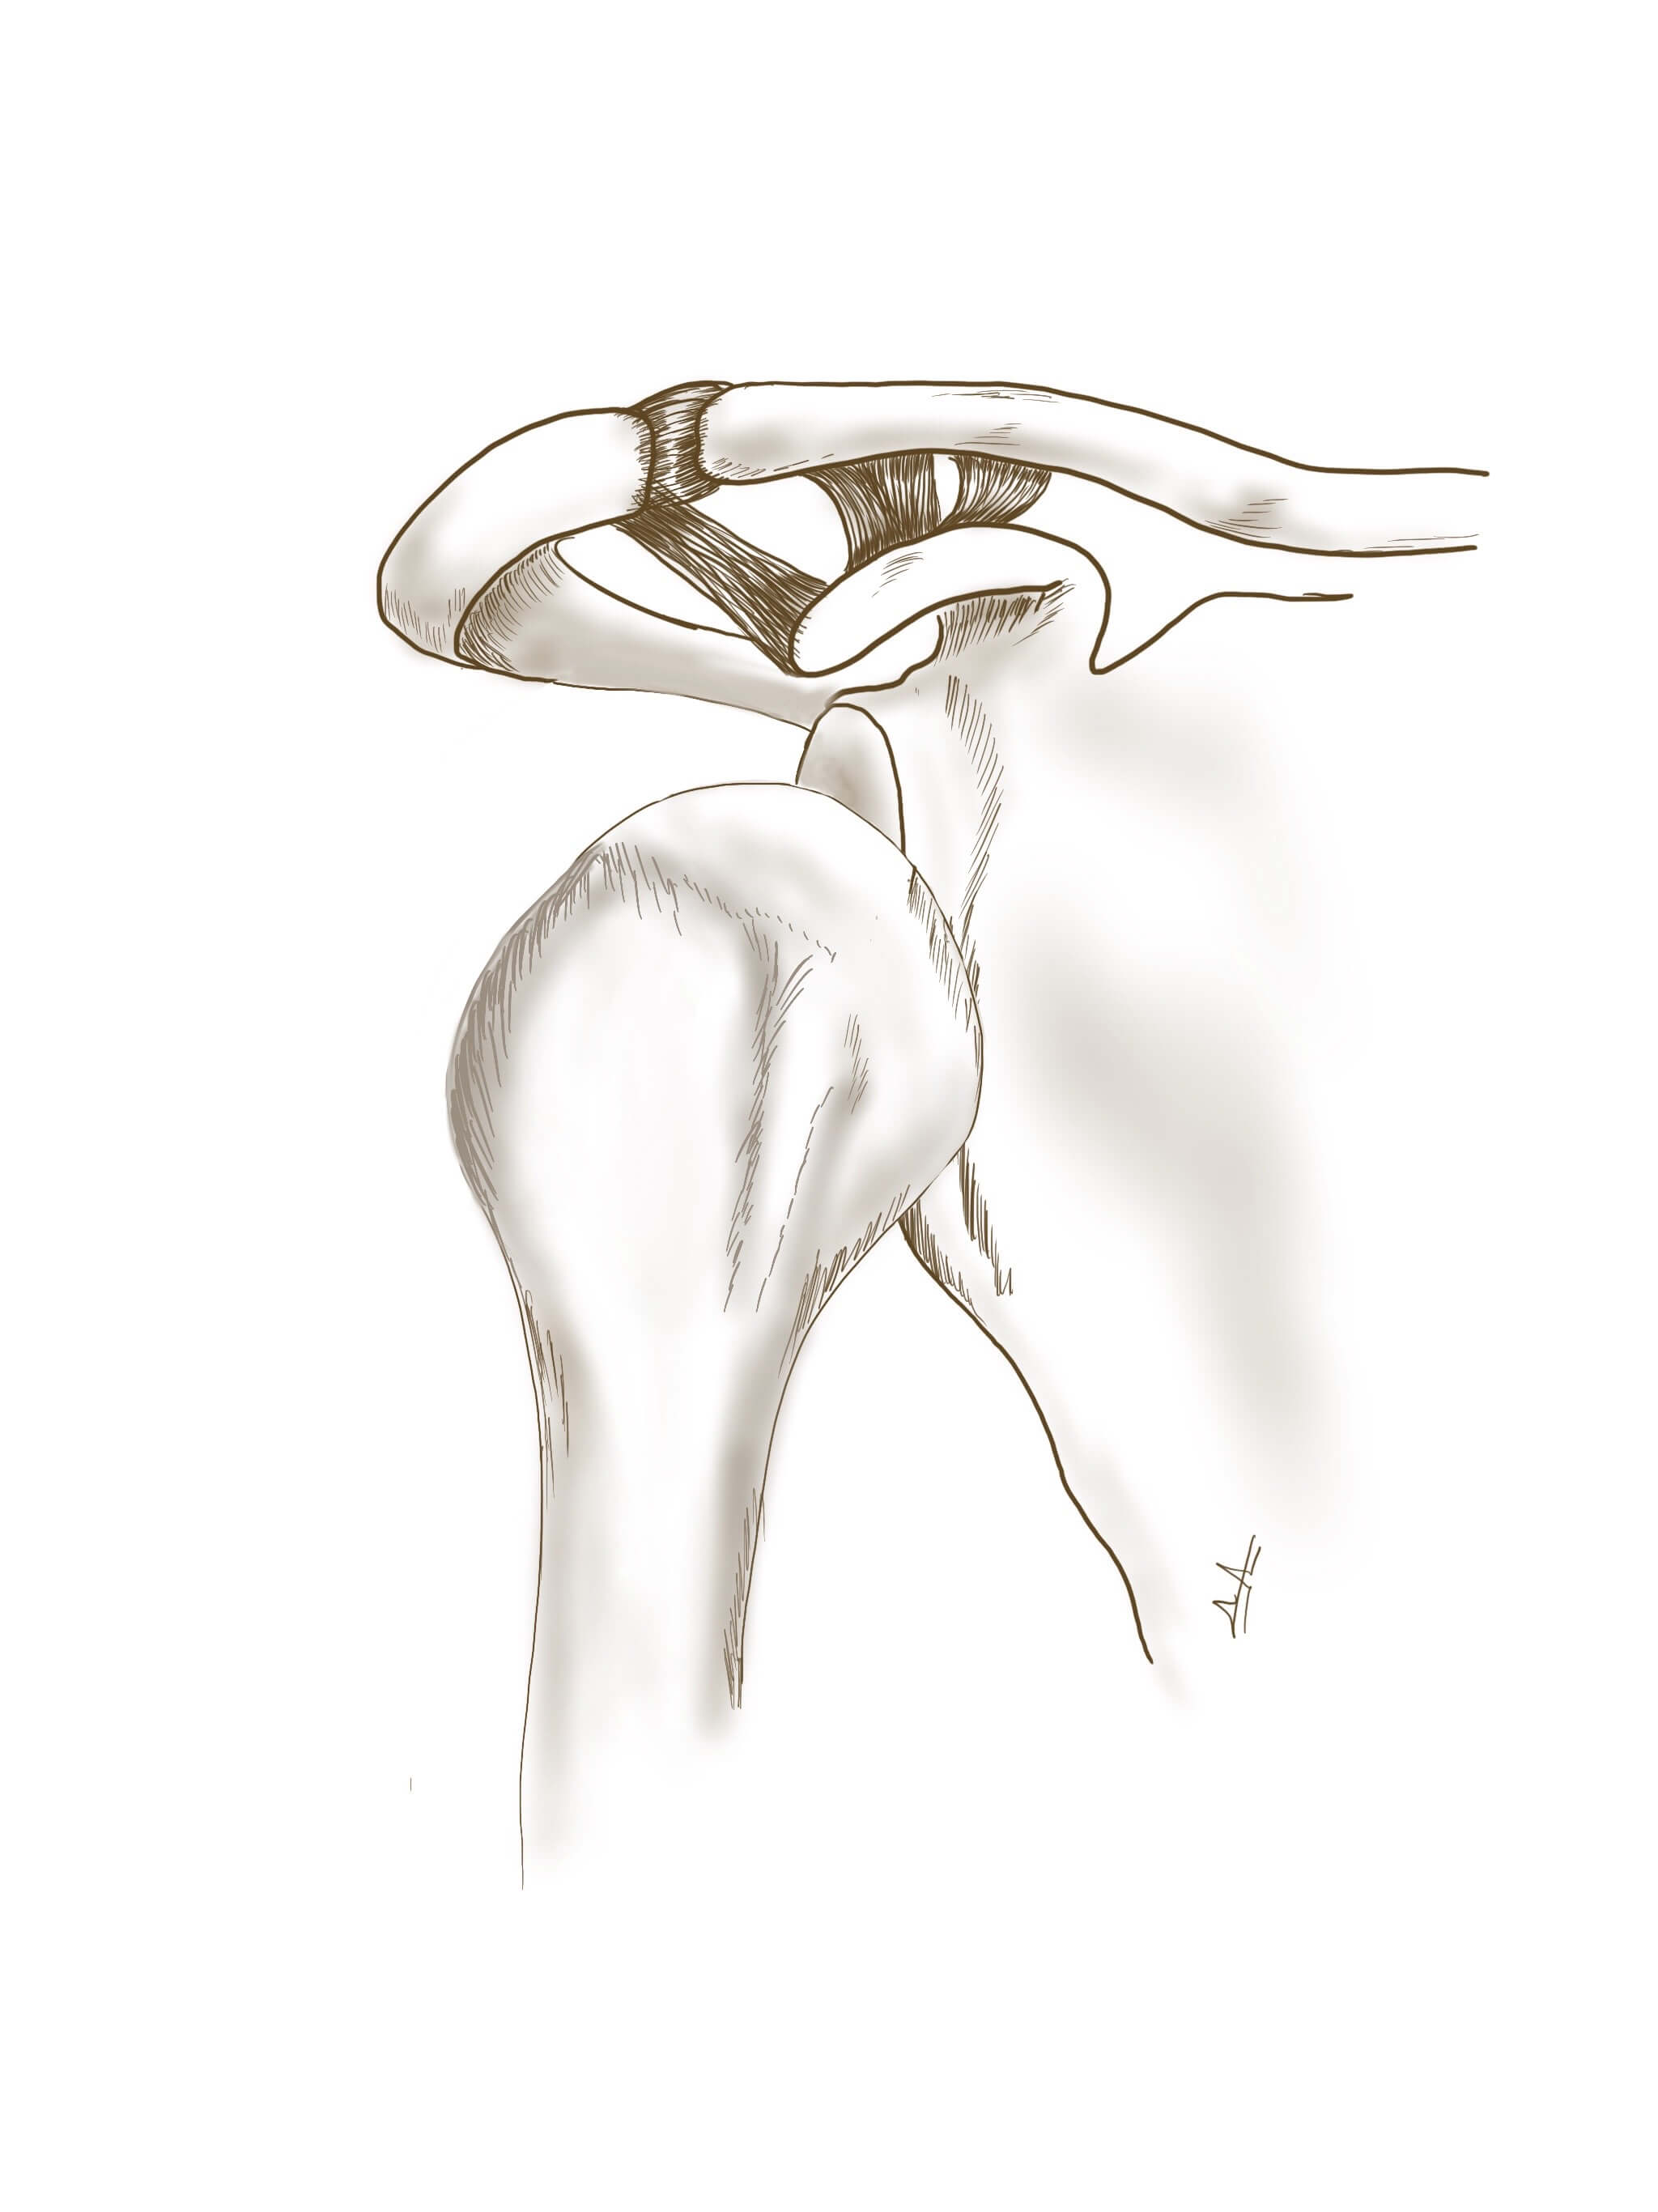

Εικ.1. Εικόνα πρόσθιου εξαρθρήματος του ώμου.

Υπάρχουν διάφοροι μέθοδοι ανάταξης όπως Milch, Stimson, Kocher, με προεξάρχουσα και πιο διαδεδομένη την Iπποκρατική μέθοδο. Για την ανάταξη με οποιαδήποτε μέθοδο απαιτείται η συνεργασία του ασθενή.Αμέσως μετά από επιτυχή ανάταξη επέρχεται μεγάλη ανακούφιση στον ασθενή. Σε κάποιες περιπτώσεις είναι δυνατό η ανάταξη να είναι ιδιαίτερα δυσχερής, όποτε γίνεται χρήση βραχείας νάρκωσης προκειμένου να επιτευχθεί χαλάρωση των μυών. Η ανάταξη πρέπει να επιβεβαιώνεται με νέο ακτινολογικό έλεγχο.